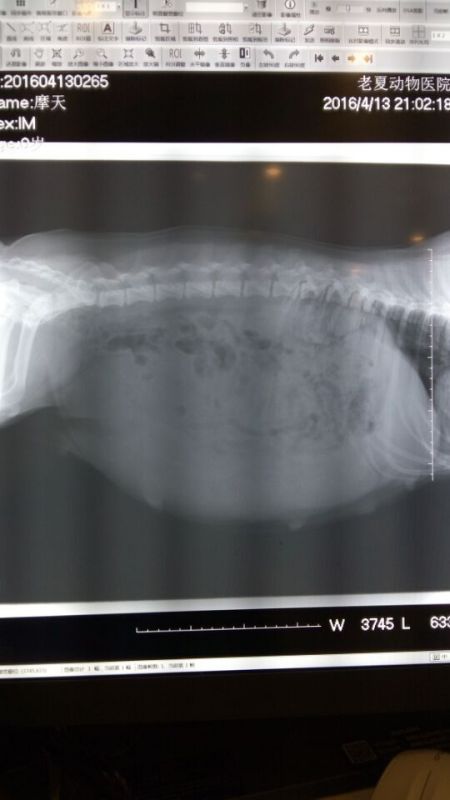

美国超级登陆冠军,中国登陆冠军“克鲁尼”直子中国登陆冠军“旺财”搭配日本登陆冠军“JACKY”直女“Magic day”,现已带胎,预产期本月28日,本胎预计为双色奶油脸,现首二选母,选公,二选公接受预定,欢迎咨询!